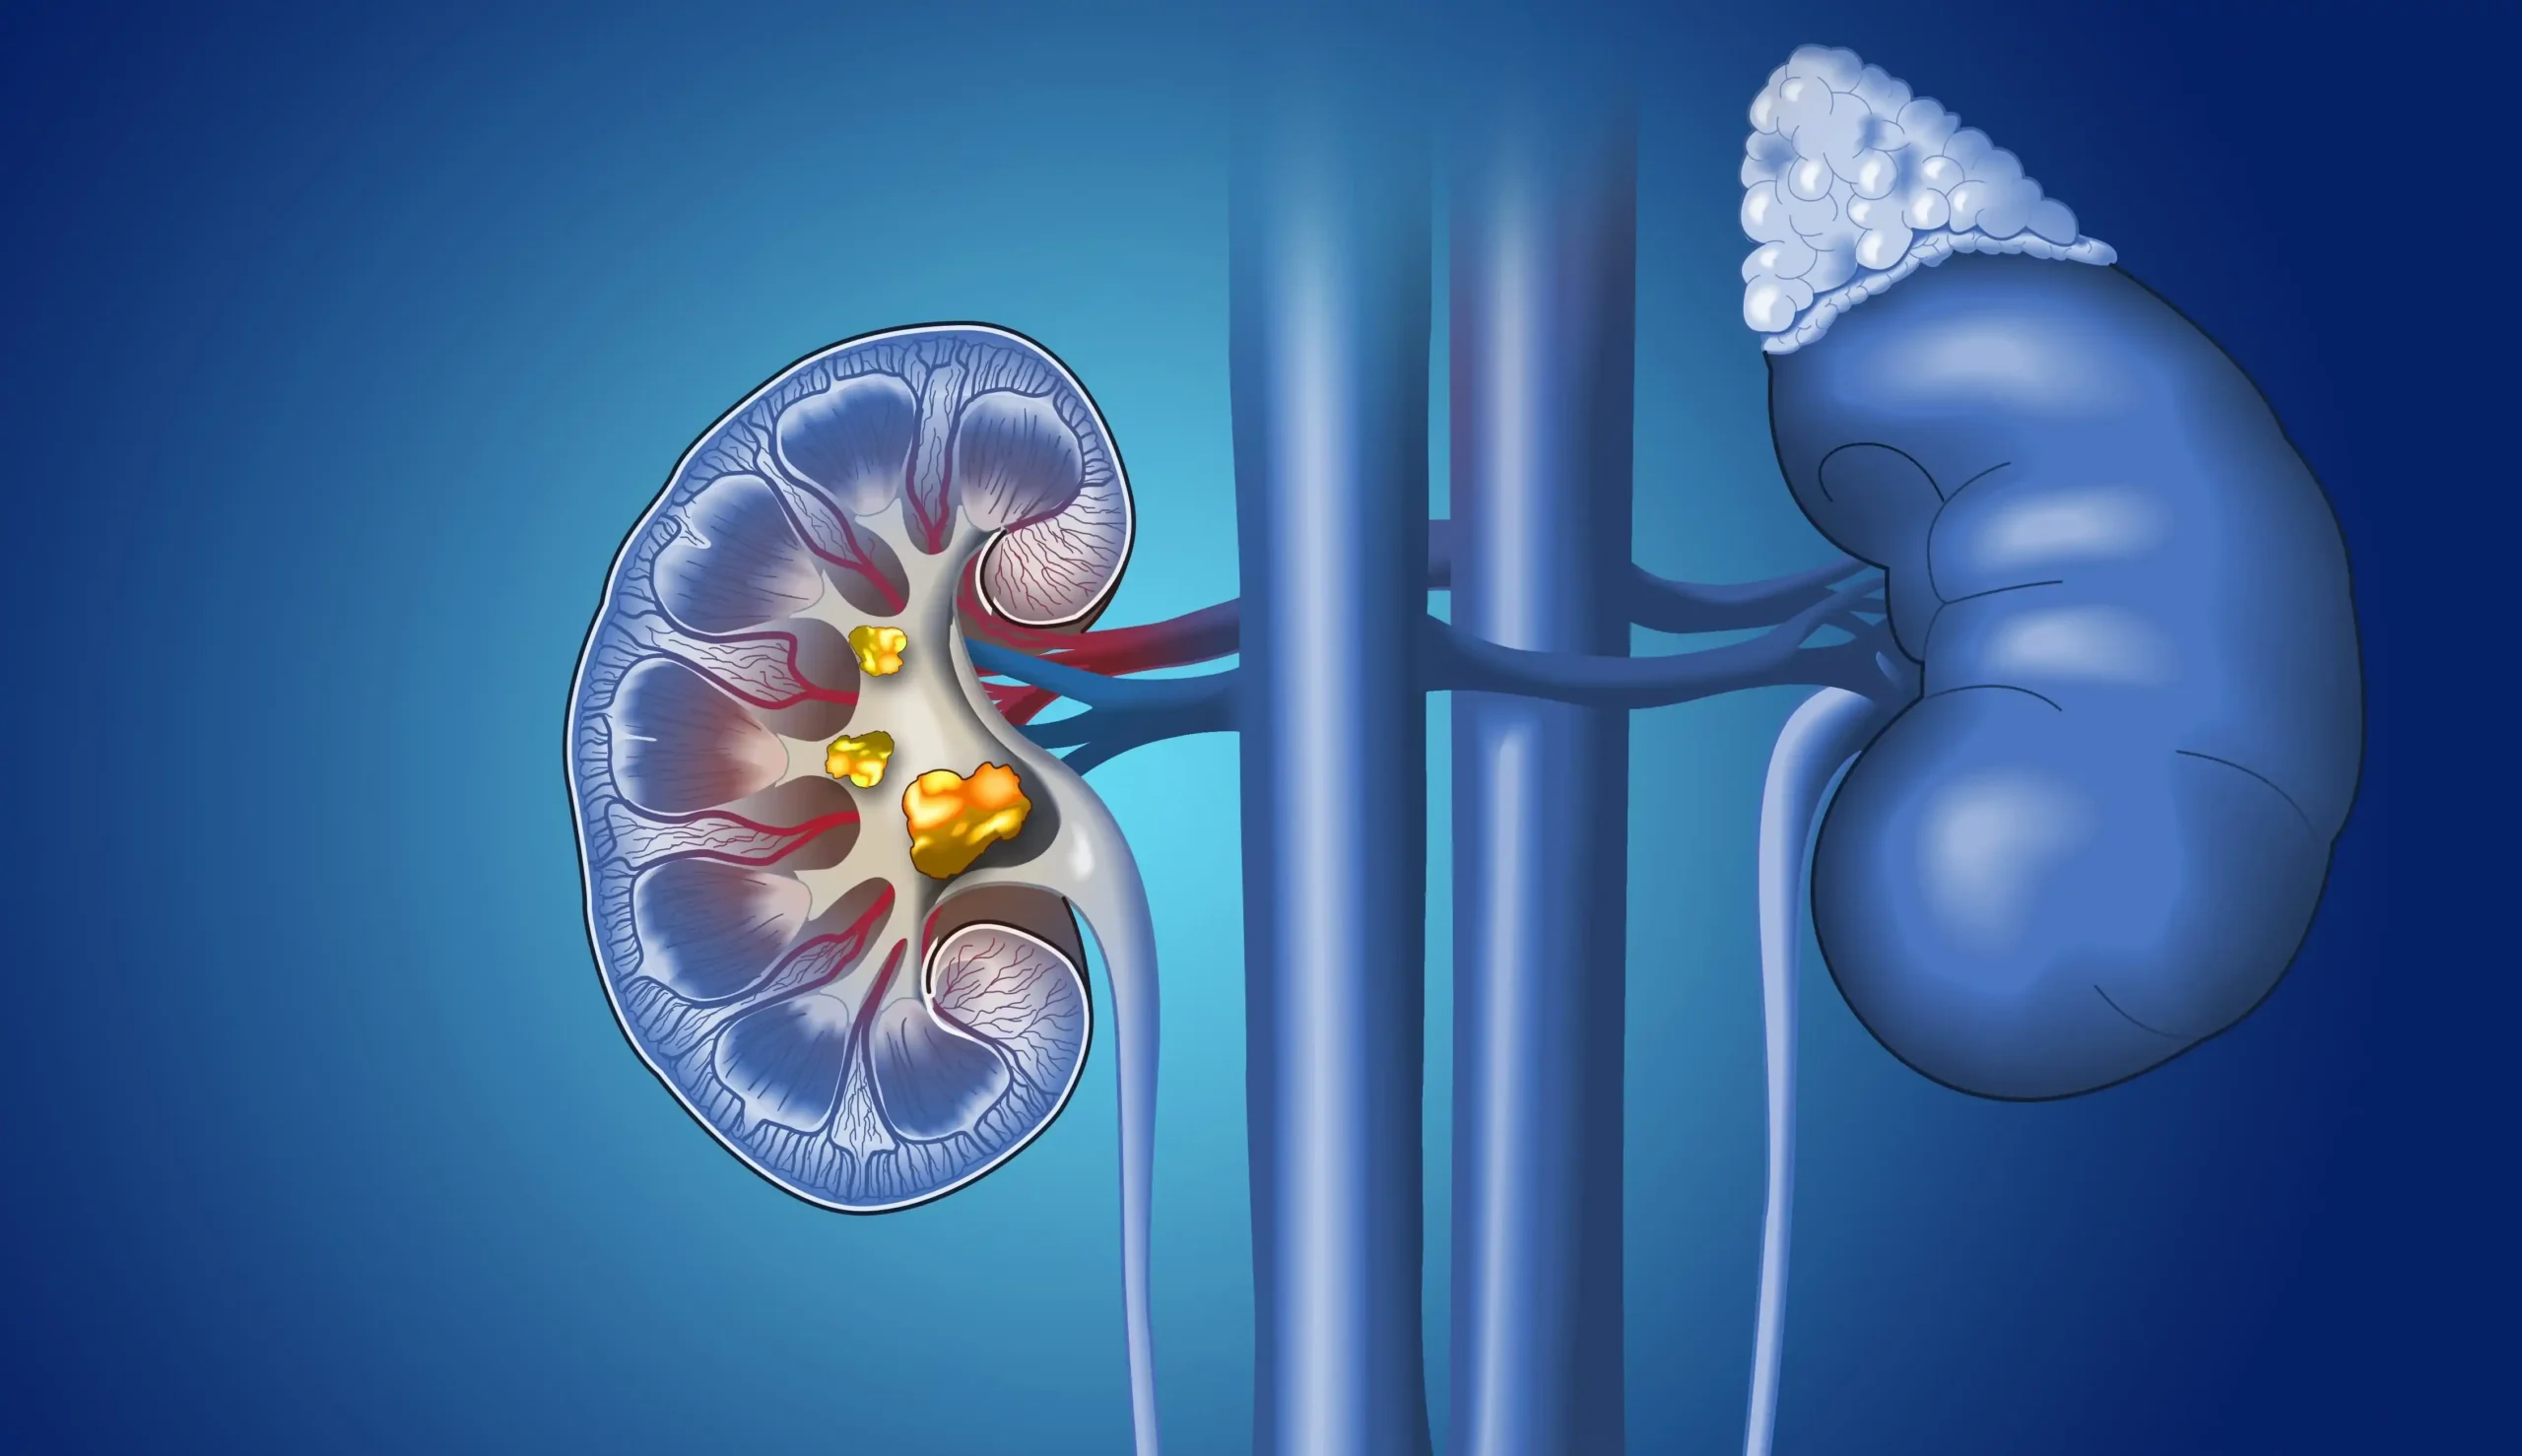

Foodinfo.az BB.LV saytına istinadla xəbər verir ki, uroloq Dmitri Juravski böyrək daşı xəstəliyinin sidiyin kimyəvi tərkibinin dəyişməsi və duzların artması nəticəsində formalaşdığını bildirib. Bu proses uzun müddət simptomsuz gedə bilər və yalnız kəskin ağrılar zamanı üzə çıxır.

Mütəxəssis qeyd edir ki, böyrək daşları müxtəlif növlərdə olur və onların yaranmasına təsir edən qidalar da fərqlənir. Ən geniş yayılan daş növlərindən biri oksalat daşlarıdır ki, bu zaman oksalat turşusu ilə zəngin məhsulların həddindən artıq qəbulu risk yaradır.

Belə məhsullara ispanaq, turşəng, cəfəri, şüyüd, çuğundur və bəzi sitrus meyvələri daxildir. Kakao da yüksək oksalat tərkibinə malikdir və xüsusilə südlə birlikdə qəbul edildikdə risk artıra bilər. Ət məhsullarının, xüsusilə qırmızı ət və yağlı bulyonların həddindən artıq qəbulu sidikdə sidik turşusunun səviyyəsini yüksəldərək daş əmələgəlmə ehtimalını artırır.